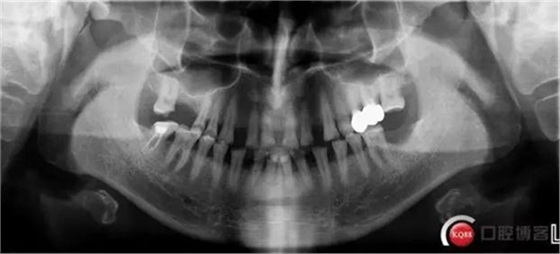

16 37 缺失

X線檢查:

CBCT檢查: